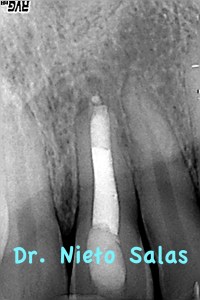

Es un tratamiento que hicimos colocando una barrera apical con M.T.A., consiguiendo un sellado apical posteriormente rellenamos el tercio medio coronal (backfilling) con gutapercha inyectada.